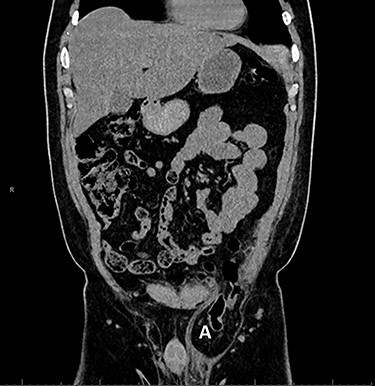

However, the patient experienced persistent swelling in the left groin. To confirm the early re-recurrence hernia, CT of the abdomen revealed a left sliding hernia with sigmoid colon (Fig. 3).

Computed tomography with sigmoid colon and solid tissue in hernia sac (A).